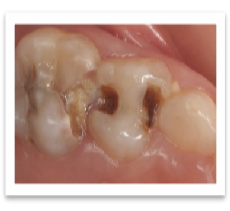

有时候,恒牙并非真正地出来晚,而是乳牙掉早了,恒牙又尚未到该萌出的时间,出现了恒牙迟迟不长的假象。造成乳牙提前脱落的原因有很多种,比较常见的有外伤或因为蛀牙导致乳牙牙根发炎。

儿童蛀牙可引起牙根发炎,影响后续牙齿替换

一般这种情况下,只要恒牙牙胚发育没有受到影响,恒牙可以在正常的萌出时间萌出;但如果造成了恒牙牙胚发育障碍,类似牙胚位置异常、牙轴发育方向异常,则还是可能导致萌出障碍的。